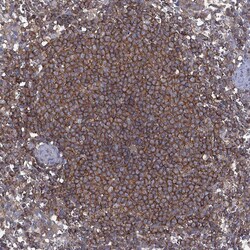

Invitrogen™ DOCK8 Polyclonal Antibody

Brand: Invitrogen™ PA5140262

Gently mix before use. Optimal concentrations and conditions for each application should be determined by the user. Immunogen sequence: INRYSSAEIR KQFTLPPNLG QYHRQSISTS GFPSLQLPQF YDPVEPVDFE GLLMTHLNSL DVQLAQELGD FTDDDLDVVF Highest antigen sequence indentity to the following orthologs: Mouse - 88%, Rat - 86%.

The Dedicator of cytokinesis protein 8 (DOCK8) is a member of the DOCK180 family of guanine nucleotide exchange factors. DOCK8 plays an essential role in humoral immune responses and is important in the proper formation of the B cell immunological synapse. Mutations in this gene result in the autosomal recessive form of the hyper-IgE syndrome.

| Immunohistochemistry (Paraffin), Western Blot | |

| Recombinant protein corresponding to Human DOCK8. Recombinant protein control fragment (Product #RP-109342). | |